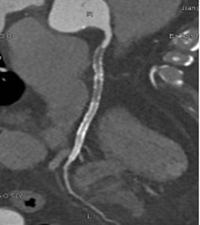

检查后,很快就能出具影像诊断结果,清晰呈现心脏血管真实状况,能让隐患无所遁形。

通过冠脉CTA,能清晰地看出多种心脏相关疾病:

还能排查冠脉畸形、血管闭塞等,为临床治疗提供精准依据。